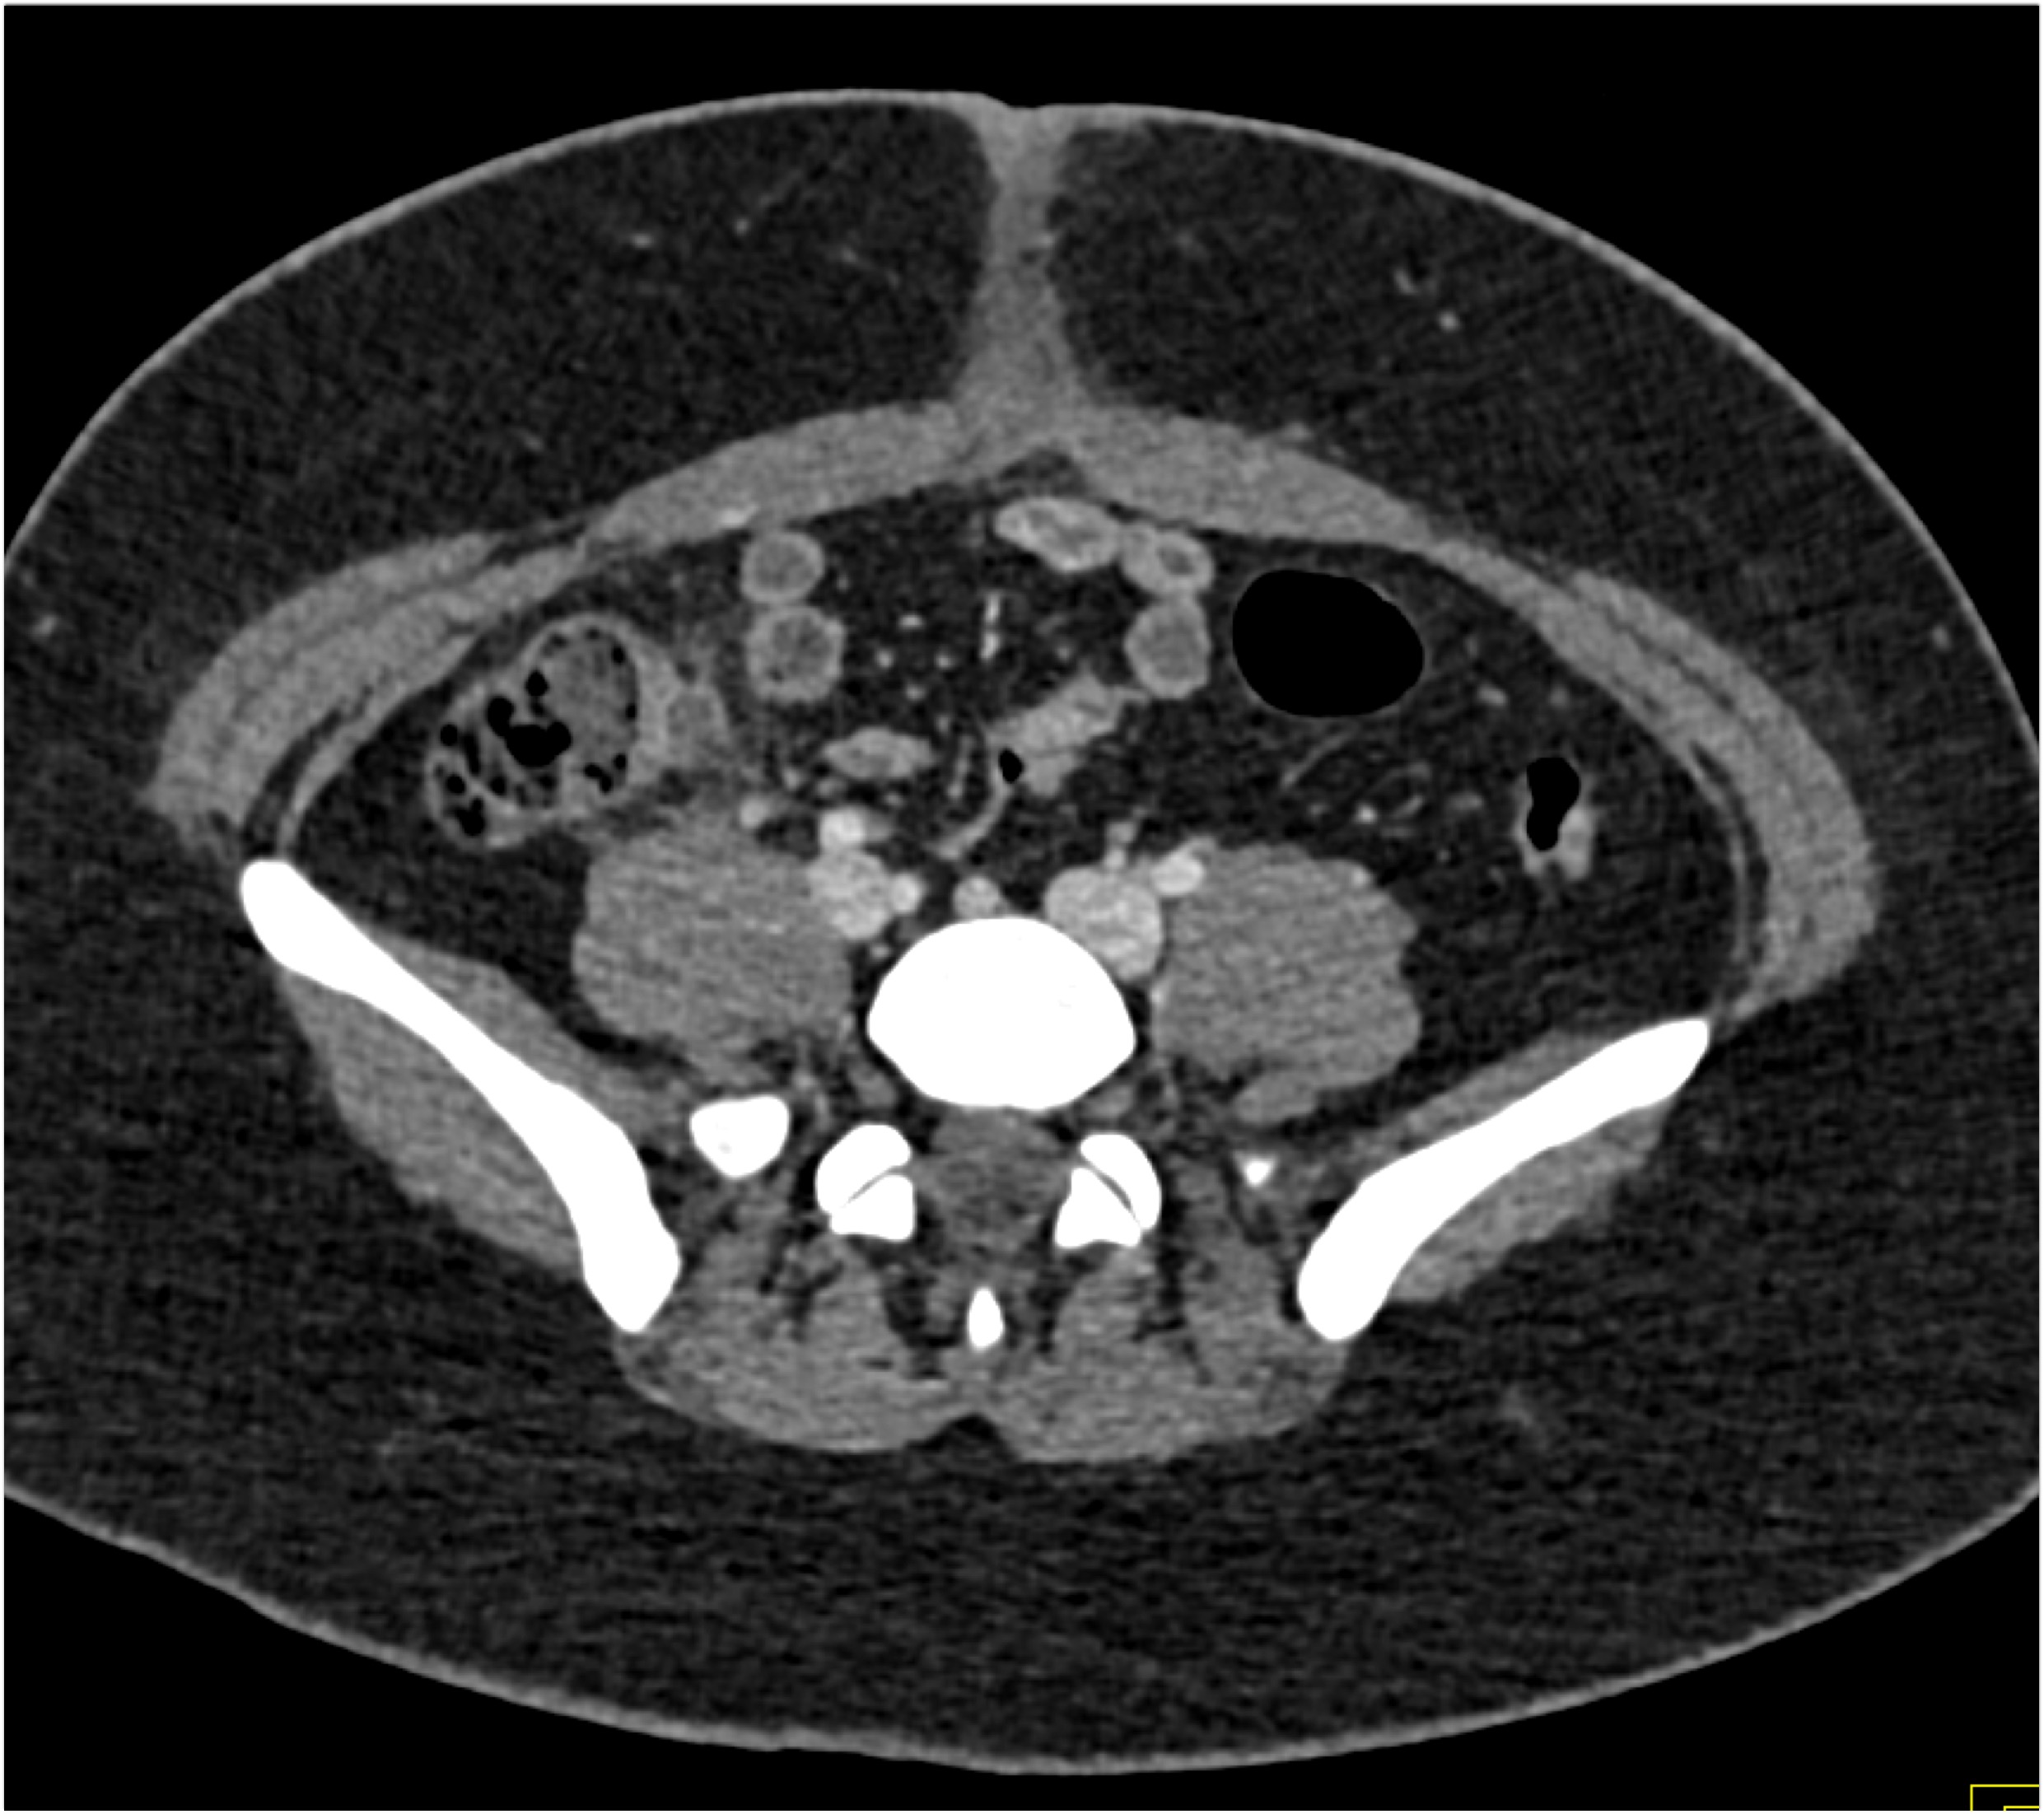

5) In this patient with Crohn’s disease and abdominal pain the critical CT finding is

stricture of colon

bowel wall thickening

active GI bleed

superimposed colon cancer